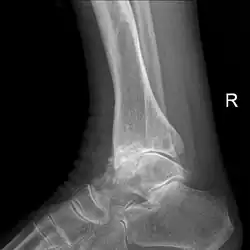

Diagnosis is made with reasonable certainty based on history and clinical examination.[52][53] X-rays may confirm the diagnosis. The typical changes seen on X-ray include: joint space narrowing, subchondral sclerosis (increased bone formation around the joint), subchondral cyst formation, and osteophytes.[54] Plain films may not correlate with the findings on physical examination or with the degree of pain.[55]

Arthrodesis (fusion) of the bones may be an option in some types of osteoarthritis. An example is ankle osteoarthritis, in which ankle fusion is considered to be the gold standard treatment in end-stage cases.[137]